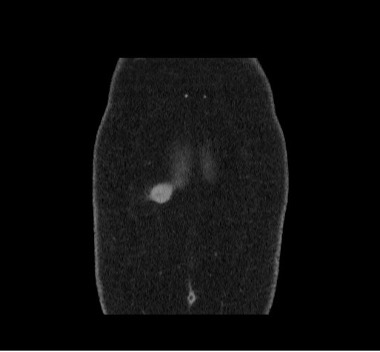

A computed tomography (CT) scan was then performed for further evaluation, results of which confirmed the presence of a mass measuring approximately 2.4 cm in diameter. The characteristics were suggestive of a possible desmoid tumor arising from the right rectus muscle and protruding into the subcutaneous fat (Figures 3-5). A wide resection of the anterior abdominal wall mass with primary abdominal wall reconstruction was performed. During the procedure, the mass appeared to be arising from either the anterior rectus aponeurosis or the rectus muscle, measuring approximately 3.0 to 3.5 cm at its widest diameter.

Figure 3. A computed tomography scan of the abdomen and pelvis in the coronal plane shows the tumor’s location.